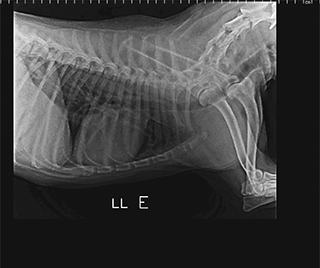

Radiologia Digital Direta / Digital Radiography

As radiografias geradas digitalmente podem ser transmitidas para iPad Apple®, notebooks e smartphones.

iPad com tela Retina Apple® possibilita a visualização das imagens com maior qualidade diagnóstica.

O treinamento aborda a geração das radiografias, a edição digital das imagens, e também a

escolha adequada de técnicas radiográficas como kilovoltagem, corrente elétrica e tempo de exposição.